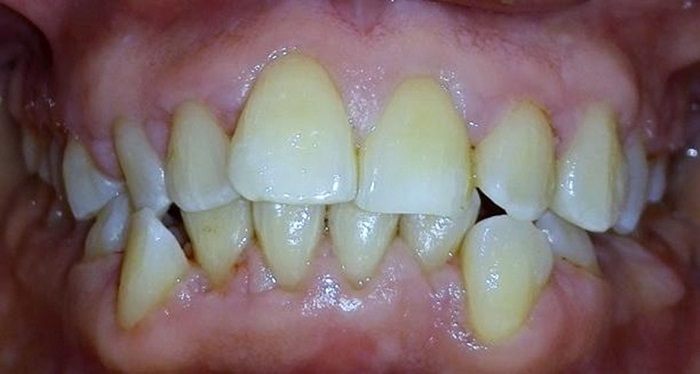

Entre los antecedentes odontológicos se reportaron cuatro gingivectomías entre 2004 y 2008. En el examen clínico extraoral la paciente evidenciaba quintos asimétricos, tercio medio disminuido, perfil convexo e incompetencia labial. En el examen clínico intraoral se registró sobremordida horizontal y vertical, malposiciones y apiñamiento dental. Periodontalmente, se observó aumento en el volumen del tejido gingival en las superficies vestibulares, palatinas y linguales de incisivos, caninos y premolares. El sondaje reveló bolsas gingivales con un rango de profundidad de 4 a 6 mm, acompañado de eritema, sangrado y cálculos subgingivales. La paciente tenía una higiene oral deficiente con un porcentaje de placa del 84,3 %, según el Índice de O’Leary (figura 1). Se notificó que su frecuencia de cepillado era de una vez al día y que no utilizaba elementos complementarios de higiene oral. La figura 2 corresponde a la radiografía panorámica en la que se observan crestas óseas de altura normal.

La fase higiénica se inició el 15 de marzo de 2015 y se centró en la motivación en salud oral para lograr un control estricto de placa. Se instruyó a la paciente en el uso de cepillo eléctrico y aditamentos para uso de seda dental, los cuales se sugirieron después de interconsulta con una odontóloga especialista en manejo de pacientes con discapacidad. Los controles de placa mostraron porcentajes del 44,1 %, 37,2 % y 35,8 % durante el entrenamiento en higiene oral. Se realizó raspaje supra y subgingival generalizado y pulido coronal. Al mes, se revaluaron los tejidos y se encontró un mejor índice de placa (22,1 %), así como disminución de la inflamación (figura 3). Se decidió realizar cirugía periodontal bajo sedación con óxido nitroso en la Universidad El Bosque de Bogotá. Se tomaron impresiones de ambos maxilares para colocar placas de presión en acetato de 0,16.